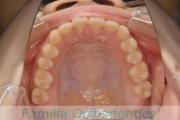

No.22V-409

- 叢生

- 16歳

- 女性

- 44

- 8|58

- FEA

- 86万円

八重歯を治したいということで来院されました。下あごの左ずれのある上顎前突(出っ歯)・叢生(でこぼこ)でしたので、上は左右から、下はで左のみ小臼歯を抜歯して、歯科矯正用アンカースクリューとマルチブラケット法にて治療を行いました。2年強、30回程度の通院が必要でした。

上下とも前歯の叢生(でこぼこ、凹凸、ガタガタ)があるため、保定を怠ると後戻りのリスクがあります。

- ≫治療後

上顎

下顎